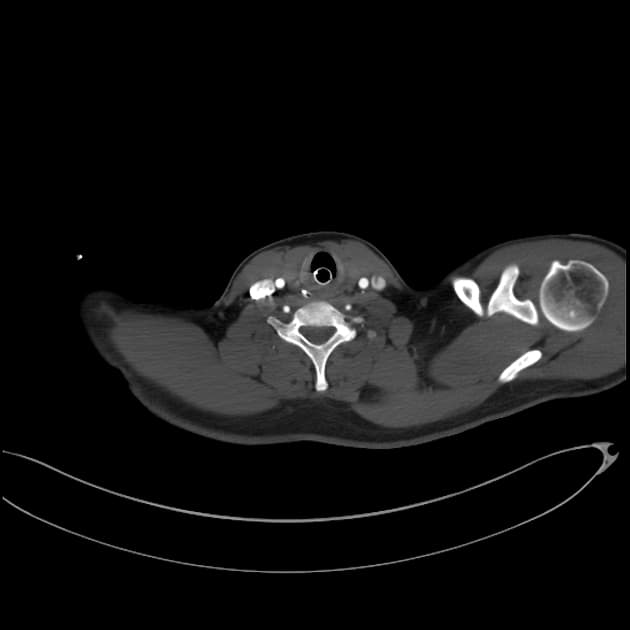

- Phình động mạch chủ lên (ascendant aorta aneurysm) >50 mm.

- Ống động mạch còn ống (patent ductus arteriosus), dạng kéo dài (elongated type), có hình ảnh thuốc cản quang đổ vào thân động mạch phổi giãn vừa (shunt trái sang phải - left to right shunt).

- Nhĩ trái giãn, kèm dày vách liên thuỳ và dày quanh phế quản - mạch máu, phù hợp với phù do tim nhẹ (mild cardiogenic edema).